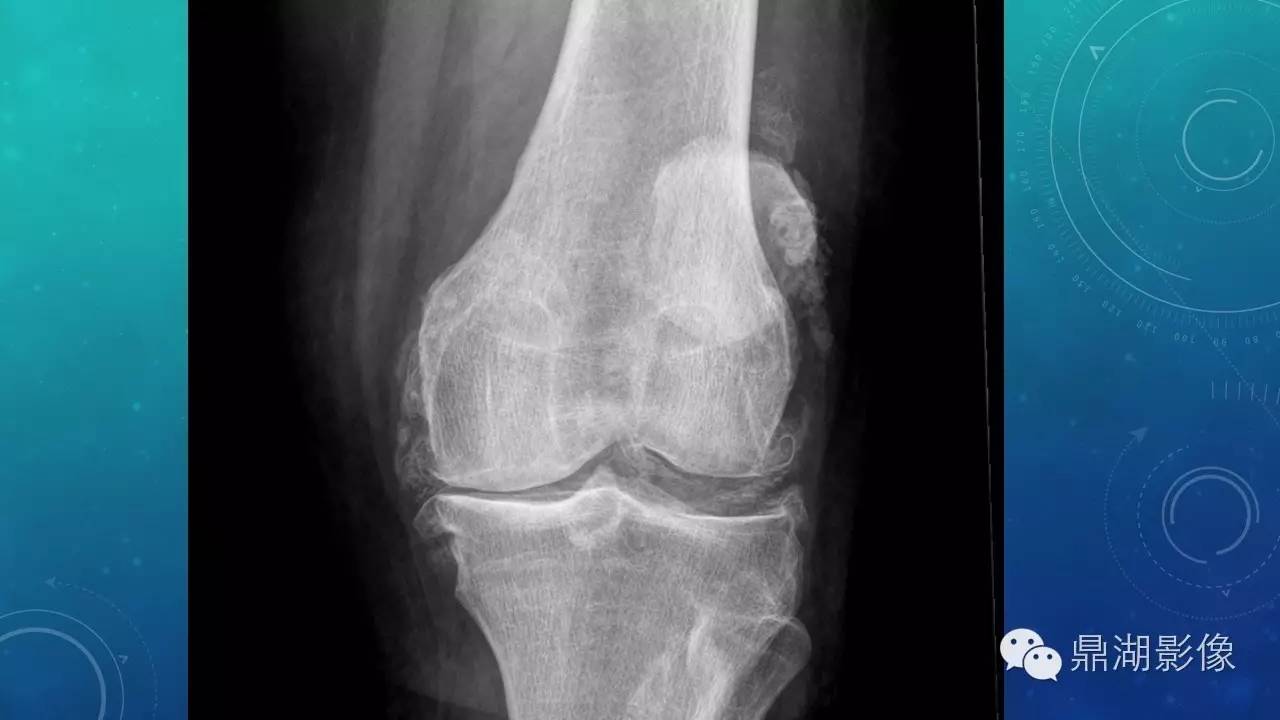

软组织钙化(的鉴别)